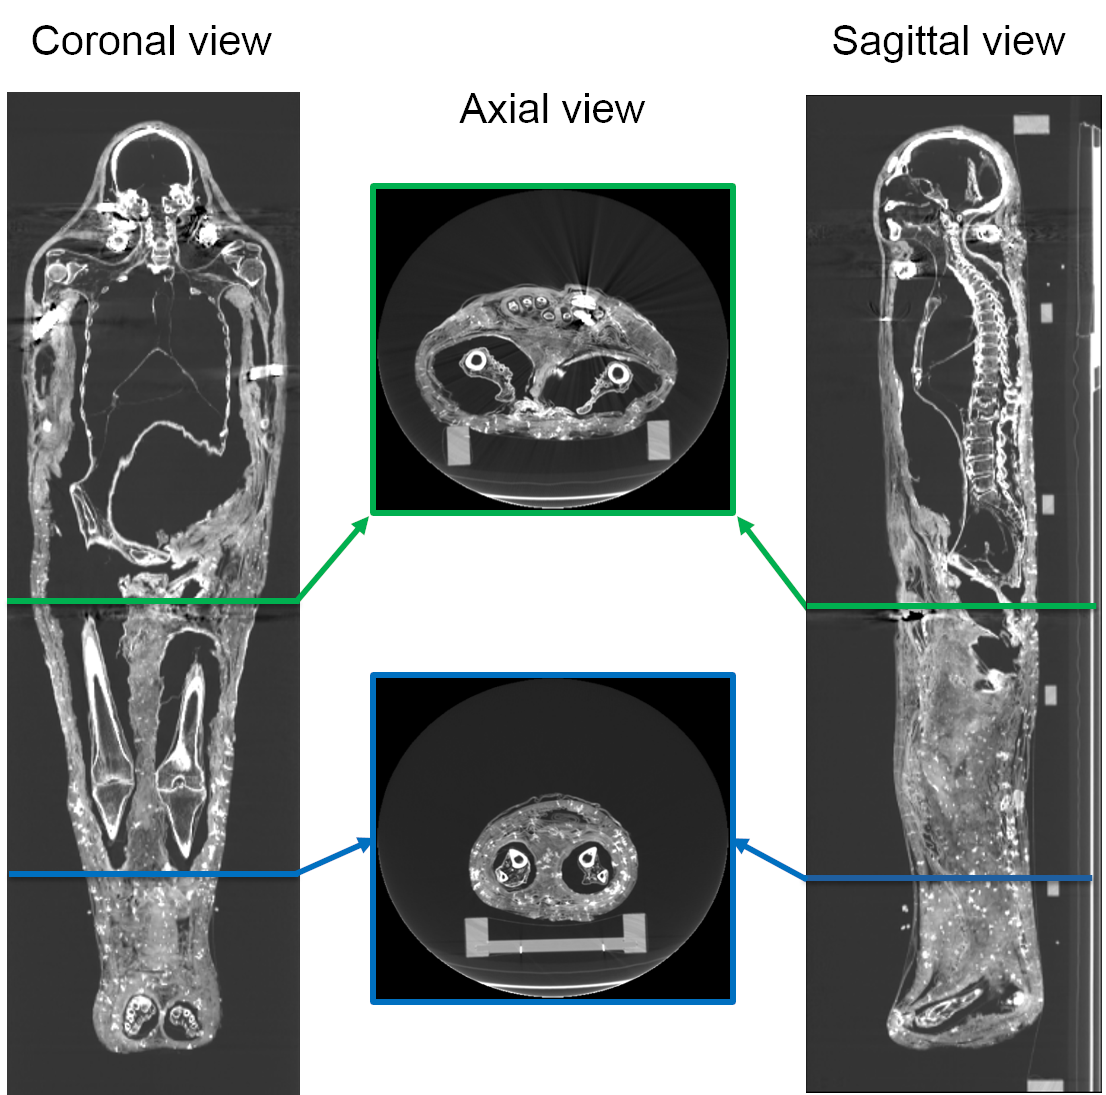

In Fig. 2, we show a qualitative example of our input data, i.e. the scan of an ancient human mummy from coronal, sagittal and axial viewpoints, and a detailed description is reported in Sec. III-A. Here, we would like to stress upon the complexity of the data. It is evident from Fig. 2 that at some locations, bandage tissue is adjacent to the body while both having very similar radiodensity, which makes the problem challenging.

Refer to caption

Figure 2: Example of coronal, axial and sagittal views of the CT scan of a human mummy [6] (contrast enhanced for better visualization).